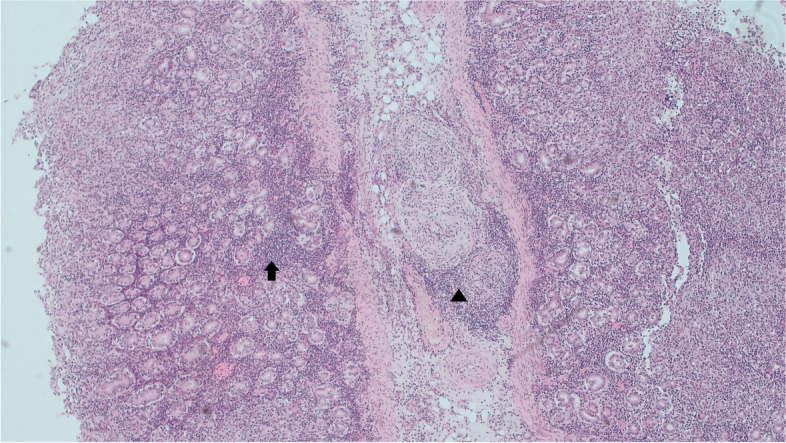

Case presentation: Using similar methods this case study reports on the findings of the first reported cases in an Irish Flock of MCF- like systemic necrotizing vasculitis in sheep associated with OvHV-2. Sheep A, a 16-month-old Texel-cross hogget displayed signs of ill- thrift, Sheep B, a nine-month-old Belclare-cross lamb, was found dead having displayed no obvious symptoms. Both cases occurred on the same farm, however the animals were not related. Lymphohistiocytic vasculitis of various tissues was the predominant histopathological finding in both animals.